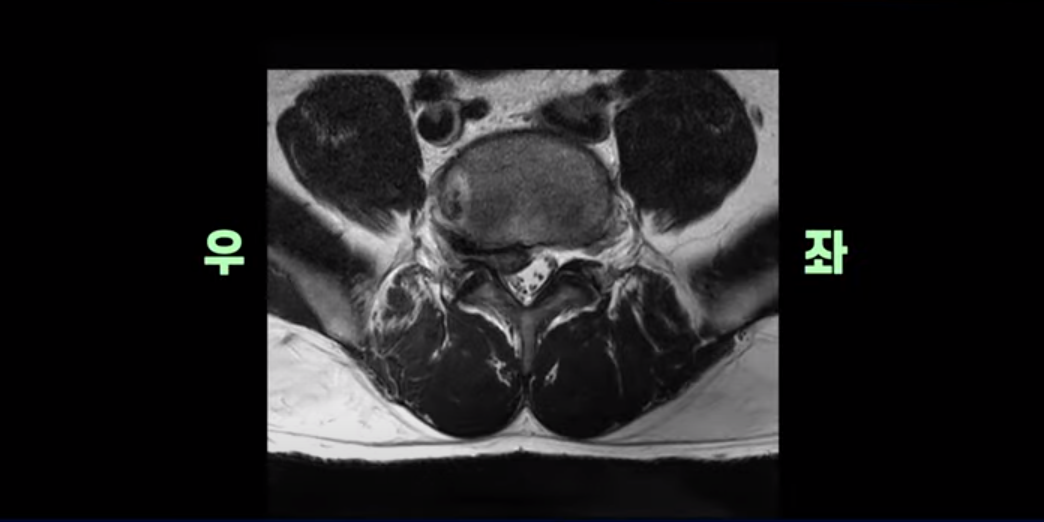

횡단면을 보면 우리 병원 치료 후기에 있는 다른 디스크 파열 환자분들에 비해서는 파열이 덜 심해 보일 수도 있지만,

이분은 파열이 오른쪽으로 치우쳐 신경이 빠져나가는 추간공을 완전히 막고 있습니다.

다른 신경 구멍들은 열려있는데 비해 5번 1번 구멍은 까맣게 막혀있습니다.